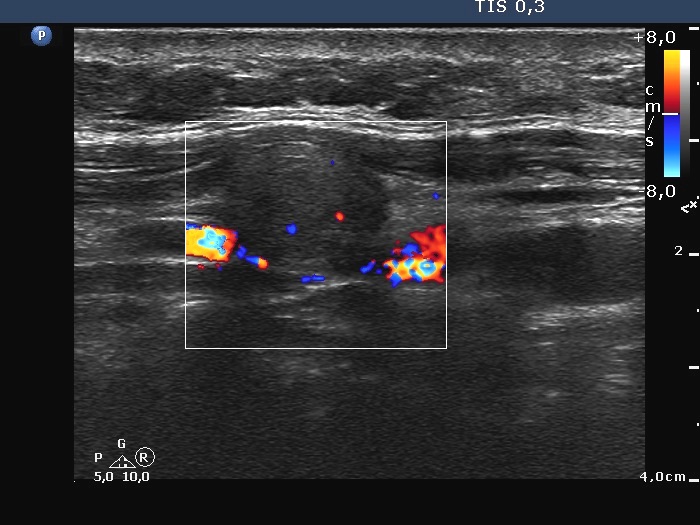

Ultrasonography: there was no parenchyma in the thyroid beds. Lateral to the right lobe there were several enlarged lymph nodes.

Cytological diagnosis: medullary carcinoma.